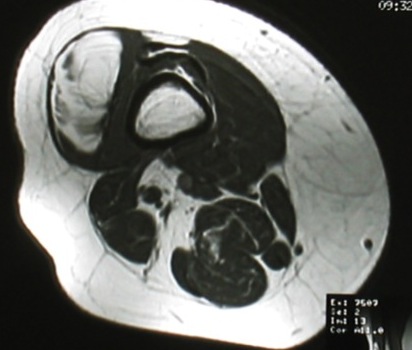

MRI

Same signal intensity as surrounding fat

Intra-muscular lipoma